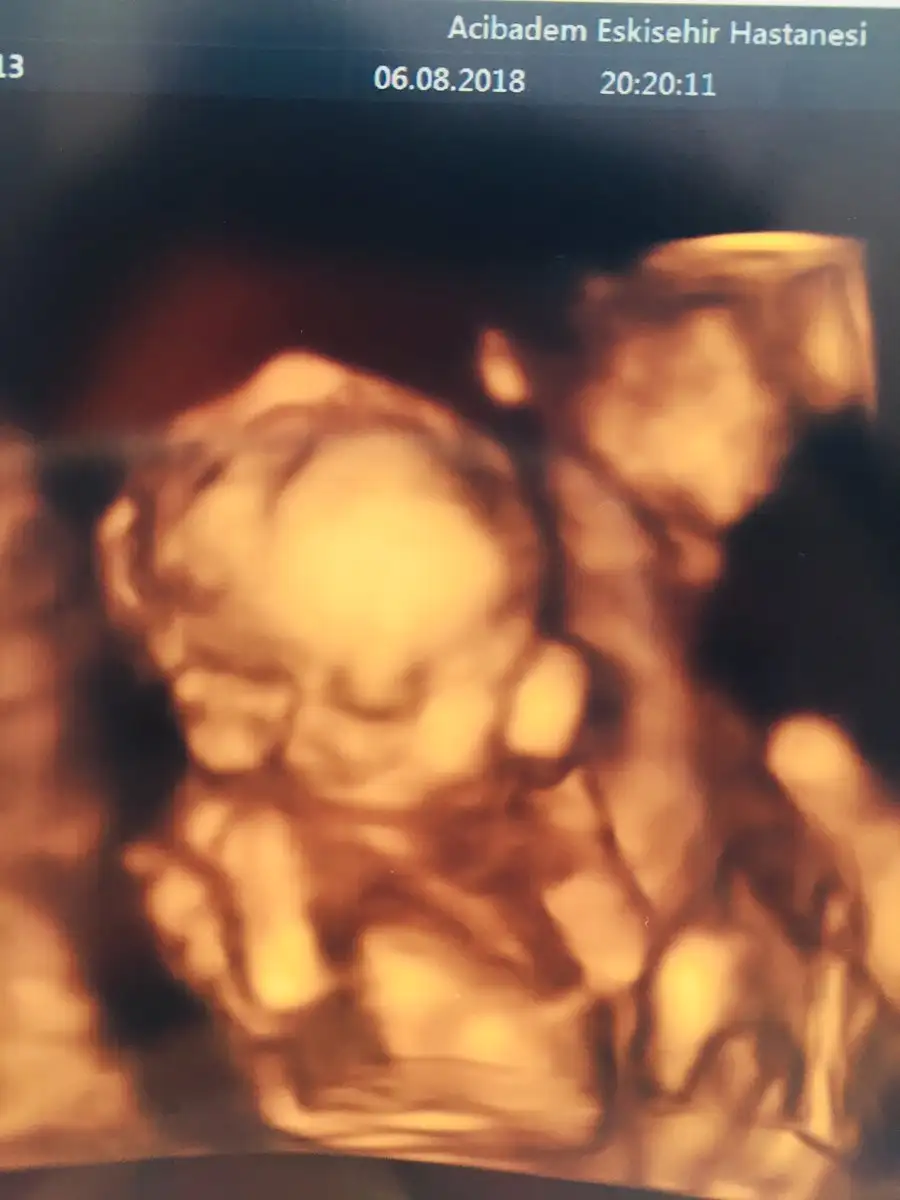

Oyyy minikkyaa bızım renklı pozlarımza bakın bugune dek bunları aldık 13haftalık biri dha 7cm orda

Bana da doktorum her gidişimde renkli görüntü verdi canım. Her defasında büyüdüğünü görmek çok güzel :)gecen bır arkadasıma da soyledım ankarada O. Ve gayet pahalı bır hastane. kadın renkli göstermemıs 17.haftada bıde dedım neden ses cıkarmıyorsun. ha şu da var benım hastaneme eşimın kuzenı gıdıyor o da daha alamamıstı onun dr.u baskası. nezaman verıyor dıye sordu bana benımkı verıyor dedım 13.haftadan buyana. dr.dan dr.a degısıyor demekkı canım![]()

evetttt yaaa resmen parmak kadarkenki halinden bebişliğe kadar olan sürecj göruyoruz nekadar şanslı bir donemdeyız kımbılır bızden sonra daha ne gelısmeler olacak şu teknolojide yerler onu pozlar hep aynı gb rahat glb ıcerde meleğinBana da doktorum her gidişimde renkli görüntü verdi canım. Her defasında büyüdüğünü görmek çok güzel :)

heheh eevettt teyzesi yicezz cıksınlar daa dudaklarmız dolgunmus baya dr demiştı benm normal kalınlkta ama eşimn baya kalın dr abimiz hep babanın genlerı daha cok dıye kızdırıyor benı sagolsun heheh:)Ayyy seninkide benim ki gibi alt dudağını emiyor :)))) Yerim ben bu melekleri![]()